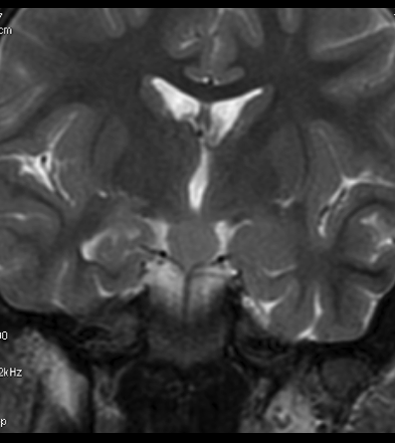

Niña de 7 años. Se solicita RM hipofisaria por pubertad precoz.

1. ¿Cuál es tu diagnóstico?

- A. Glioma hipotalámico.

- B. Histiocitosis X.

- C. Hamartoma hipotalámico.

- D. Craneofaringioma.

- E. Germinoma hipotalámico.